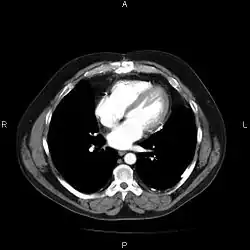

An image as stored on a picture archiving and communication system (PACS)

A picture archiving and communication system (PACS) is a medical imaging technology which provides economical storage and convenient access to images from multiple modalities (source machine types).[1] Electronic images and reports are transmitted digitally via PACS; this eliminates the need to manually file, retrieve, or transport film jackets, the folders used to store and protect X-ray film. The universal format for PACS image storage and transfer is DICOM (Digital Imaging and Communications in Medicine). Non-image data, such as scanned documents, may be incorporated using consumer industry standard formats like PDF (Portable Document Format), once encapsulated in DICOM. A PACS consists of four major components: The imaging modalities such as X-ray plain film (PF), computed tomography (CT) and magnetic resonance imaging (MRI), a secured network for the transmission of patient information, workstations for interpreting and reviewing images, and archives for the storage and retrieval of images and reports. Combined with available and emerging web technology, PACS has the ability to deliver timely and efficient access to images, interpretations, and related data. PACS reduces the physical and time barriers associated with traditional film-based image retrieval, distribution, and display.